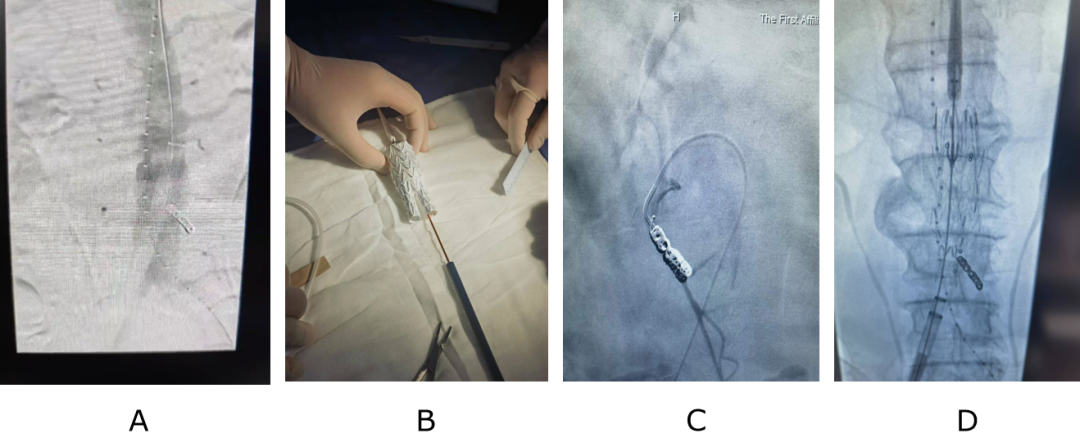

A:术前造影;B:XJZDF34120改装;C:肠下7mm,栓塞;D:主体支架释放

右侧IBD主体到位,超选、测量并导入右侧髂内支架;左侧IBD支架到位,超选、测量并导入左侧髂内支架